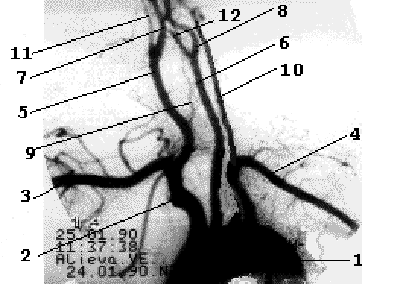

От дуги аорты отходят три основных артериальных ствола - слева общая сонная и подключичная артерии, справа - короткий брахиоцефальный ствол, который делится на правую подключичную и правую общую сонную артерии. Обе позвоночные артерии отходят от соименных подключичных артерий, являясь границей первого и второго сегментов ПКА. Общая сонная артерия у верхнего края щитовидного хряща делится на наружную сонную артерию и внутреннюю сонную артерию (рис. 1.3).

Рис 1.3

Рентгеноанатомия брахиоцефальных

ветвей дуги аорты.

1- дуга аорты, 2-

брахиоцефальный ствол, 3- правая ПКА, 4-

левая ПКА, 5- правая ОСА, 6- левая ОСА, 7-

правая ВСА, 8- левая ВСА, 9- правая ПА, 10-

левая ПА, 11- правая НСА, 12- левая НСА.